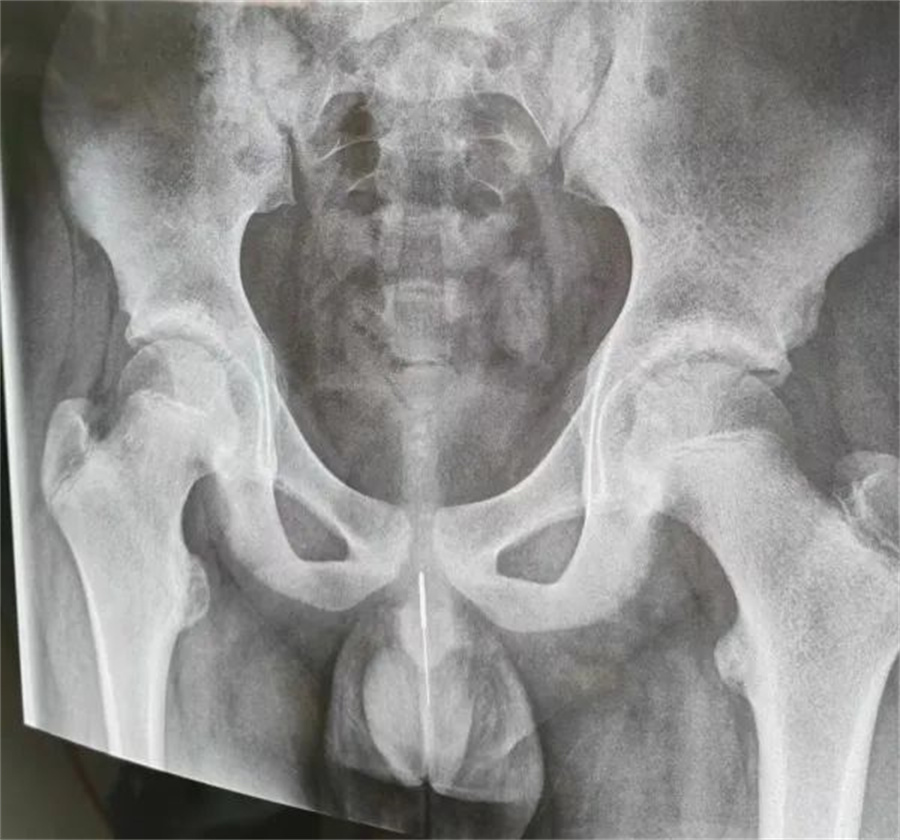

“孩子大概是中午的时候把银针塞进尿道中,因为针灸银针前段柔软纤细而末段又有增粗的螺旋状柄头,所以很难取出来。家长已经带他在当地医院拍片确诊,晚上7点多转到我们医院,当时孩子尿道口有血,疼痛难忍......”德州扑克游戏网

急诊外科接诊后立即收入院并第一时间做好手术准备,此时泌尿外科主任谢方达也紧急从家中赶到了医院,经过术前检查,确认银针卡在了接近球部尿道的部位,位置比较深,又没进入到膀胱里,如何尽快地取针成为一个颇具难度的挑战。

孩子家长和泌尿外科专家都希望用最微创的方式完成手术。但因孩子年龄小、尿道细,体重又偏大而难以实现,术中医生在保证对孩子造成伤害最小的前提下,采取隐匿小切口的方式,顺利将6.5cm的银针从尿道中刺破取出,为孩子解除了困扰,术后恢复三四天后即可顺利出院。